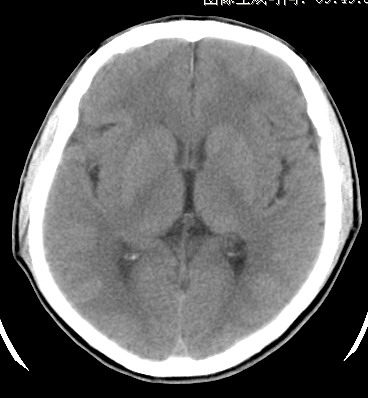

标题: CT17787:头ct,请帮忙看看右顶部有无异常 [打印本页]

标题: CT17787:头ct,请帮忙看看右顶部有无异常

男,58岁,偶有头疼

未见明显异常。右顶部低密度影为深入的脑沟。

增宽的脑沟!无异常!

是宽大的脑沟,局部不象有萎缩现象

增宽的脑沟

诊断依据:

低密度影周围脑组织边缘均有一层脑灰质覆盖。

正常啊,是对右顶增宽脑沟有疑问吗